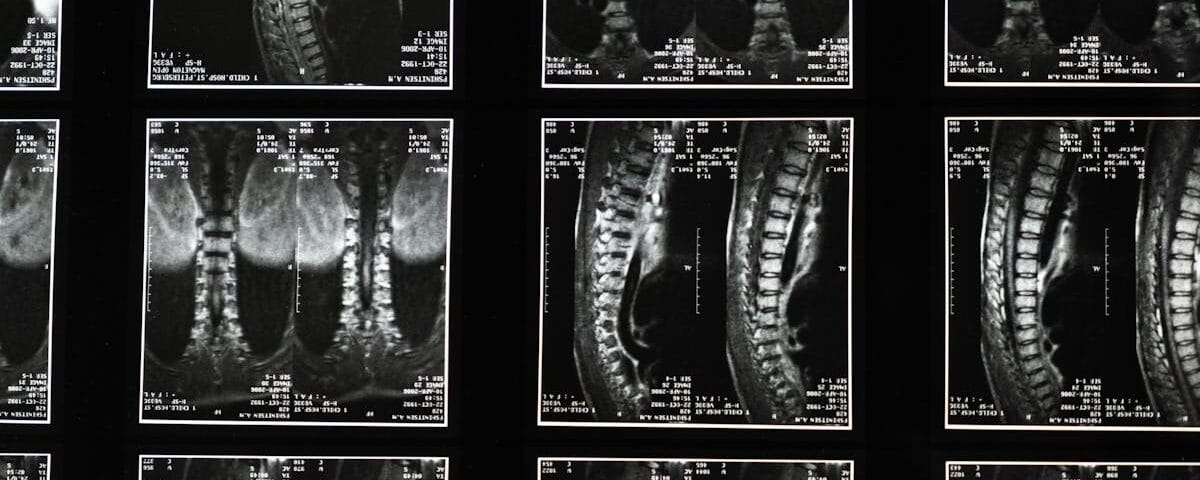

Avant d’entamer un traitement par décompression vertébrale, il est vital de réaliser une évaluation complète pour déterminer la gravité de la sténose et d’autres conditions sous-jacentes. Des examens d’imagerie, tels que des IRM ou des radiographies, peuvent être nécessaires pour visualiser l’état de la colonne vertébrale. En complément, la physiothérapie peut être recommandée pour renforcer les muscles du dos et améliorer la flexibilité.